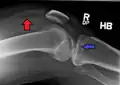

Lipohemarthrosis due to a tibial plateau fracture -

A tibial plateau fracture seen on X-ray